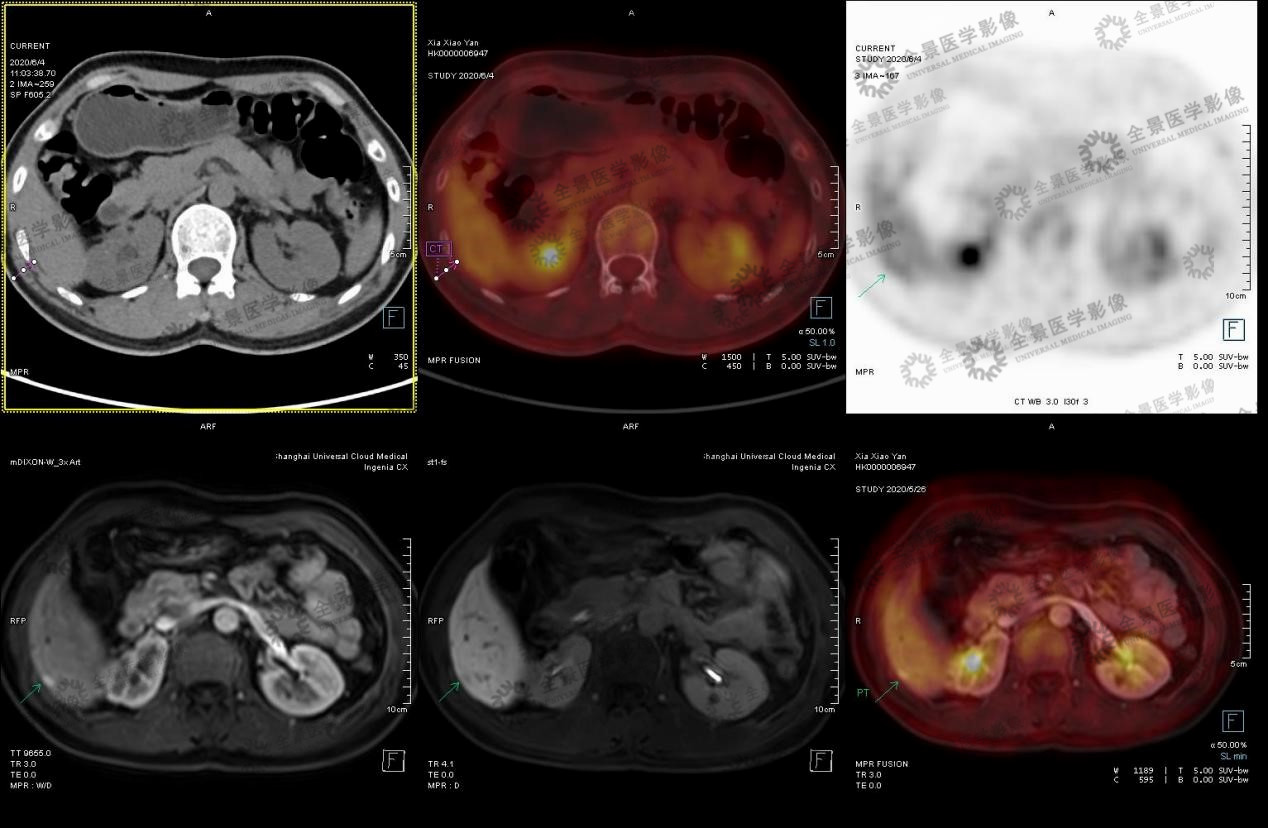

实例一

中年女性 外院体检发现肝脏小结节,乙肝病史不详。无明显不适症状。2020.5 于本中心行腹部MRI示:肝右后叶下段包膜下小结节,考虑小肝癌可能。

肝右后叶下段包膜下小结节,考虑小肝癌